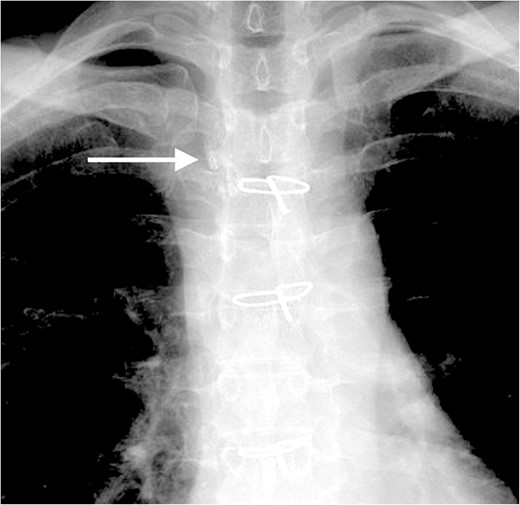

Four days after fasting, we resumed the normal diet and pleural fluid changed to slightly milky again. To specifically identify the location of and reduce the chyle leakage, lipiodol lymphography was attempted in the supine position through the right inguinal lymph nodes. The lipiodol lymphography detected the suspicious location of the chyle leakage (Fig. 4). After this procedure, the amount of pleural effusion was further reduced. Chemical pleurodesis with OK-432 was also performed just to be sure. The chest tube was removed the next day. She was discharged 10 days after re-admission. Chylothorax has not recurred 3 months post-operatively.

The lipiodol lymphography detected the suspicious location of the chyle leakage (arrow).